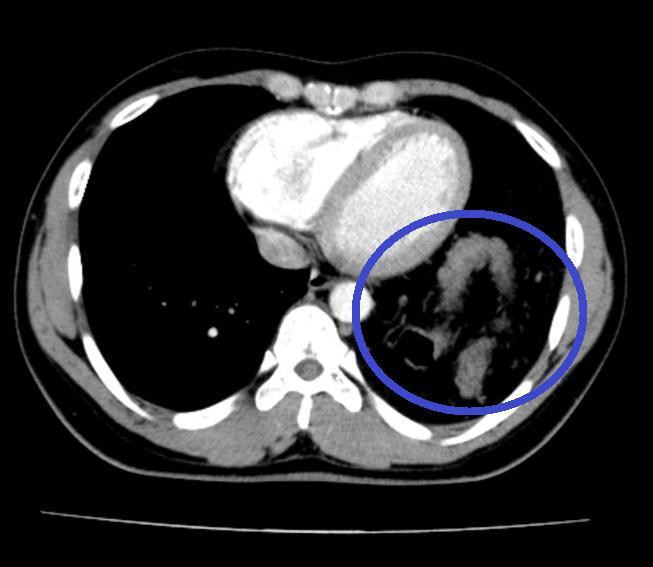

![]() |

| Đại tràng nằm trong ngực trái trên (Cắt lớp vi tính ngực). Ảnh: BS cung cấp |

Bệnh nhân được hoàn thiện thêm các xét nghiệm cận lâm sàng và hội chẩn thêm các chuyên khoa, chụp cắt lớp khẳng định có thoát vị tạng bụng qua cơ hoành lên ngực trái. Sau đó, H. được chuyển tới Khoa Phẫu thuật Tiêu hóa - Gan mật tụy để tiến hành phẫu thuật.

- Cắt lớp vi tính và cộng hưởng từ: Thấy vị trí gián đoạn của cơ hoành, hình ảnh các tạng thoát vị, giúp đánh giá được thể bệnh và đưa ra phương án điều trị phù hợp.